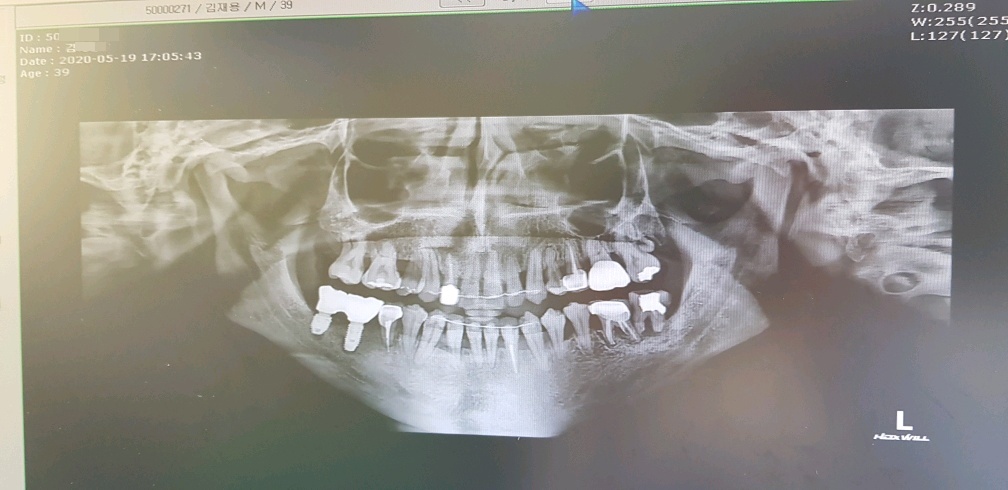

임플란트만 벌써 4개째 수술...

전에 한번 임플란트 전문 치과를 방문해서 어금니와, 바로 앞 치아 두개를 같이 수술했었는데

화면상에서 왼쪽치아 두개는 잘 됐다고 해서 다행인데

오른쪽 어금니 치아 두개다가 상태가 영...심각하다..